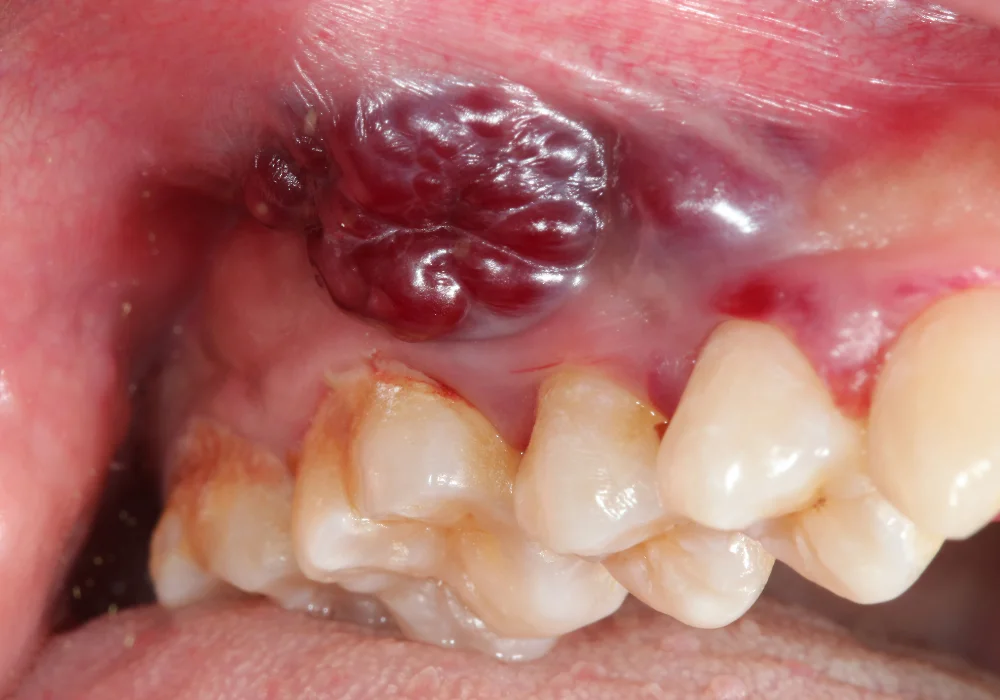

Cirugías de quistes o tumores orales